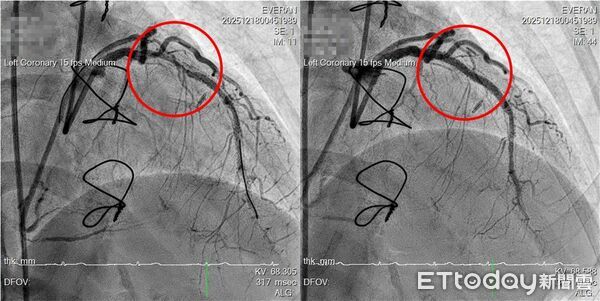

▲相較手術前(左圖),手術後(右圖)紅圈的血管血流明顯通暢。(圖/記者游瓊華翻攝)

在IVL血管內震波碎石術輔助下,醫療團隊順利為李小姐完成藥物支架置放,血流恢復通暢,長期困擾的胸悶與背痛症狀明顯改善,成功解除多年來反覆出現的「心頭之患」。